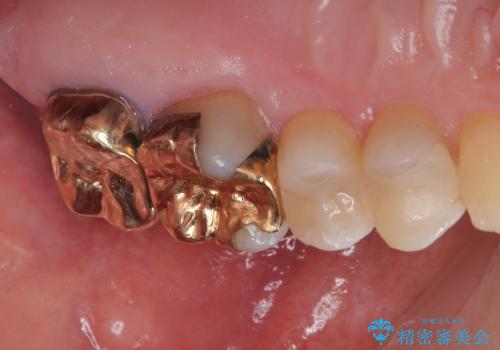

銀歯が取れた セラミックインレー修復

- 銀歯が取れたとのことで来院された患者様です。咬み合わせが強い方なので、ゴールドインレーでの治療をお勧めしましたが、ご本人の希望により審美性に優れたセラミックインレーでの治療を行っていくことにしました。